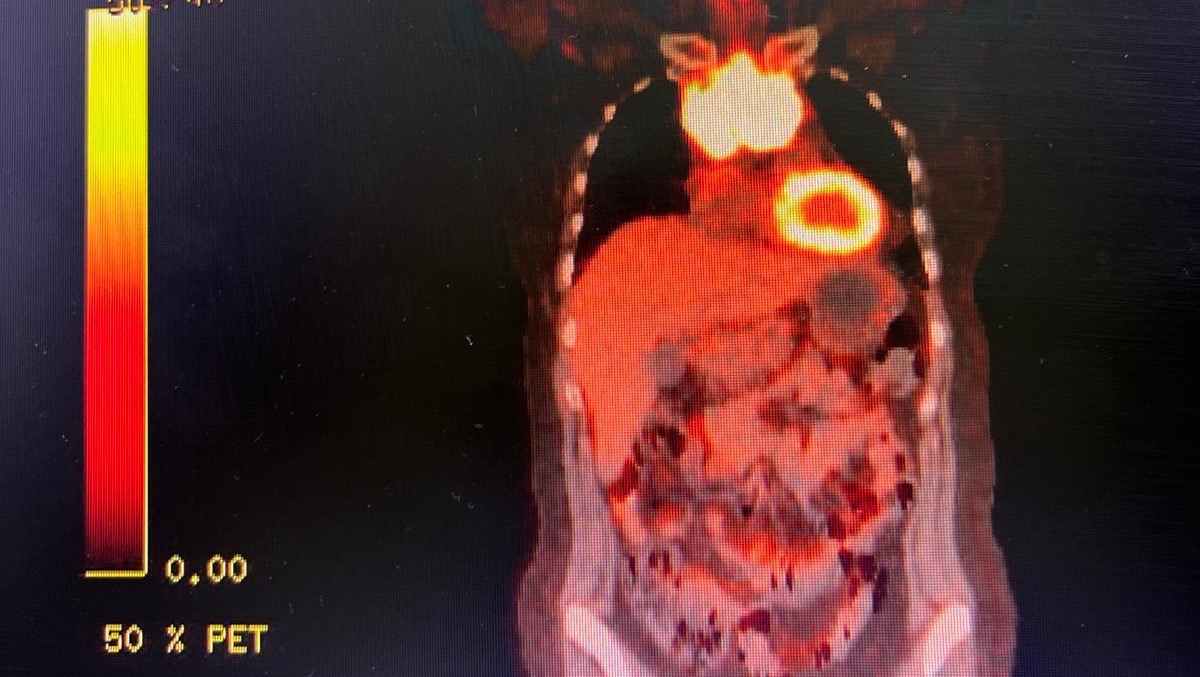

Hace unos meses me detectaron un tumor en el mediastino, después recibí el diagnóstico oficial que me sacudió por completo, linfoma no Hodgkin de células grandes B de alto grado. Desde entonces, he pasado por consultas médicas, exámenes, tratamientos, medicamentos y procedimientos que son indispensables para mi recuperación, pero también muy costosos. A pesar de dar mi mejor esfuerzo, los gastos han ido aumentando y ya no puedo afrontarlos sola.

A few months ago, a tumor was found in my mediastinum. Later, I received the official diagnosis that completely shook my world: high-grade diffuse large B-cell non-Hodgkin lymphoma. Since then, I have gone through medical appointments, tests, treatments, medications, and procedures that are essential for my recovery—but also very expensive. Despite giving my best effort, the costs keep rising, and I can no longer face them on my own.